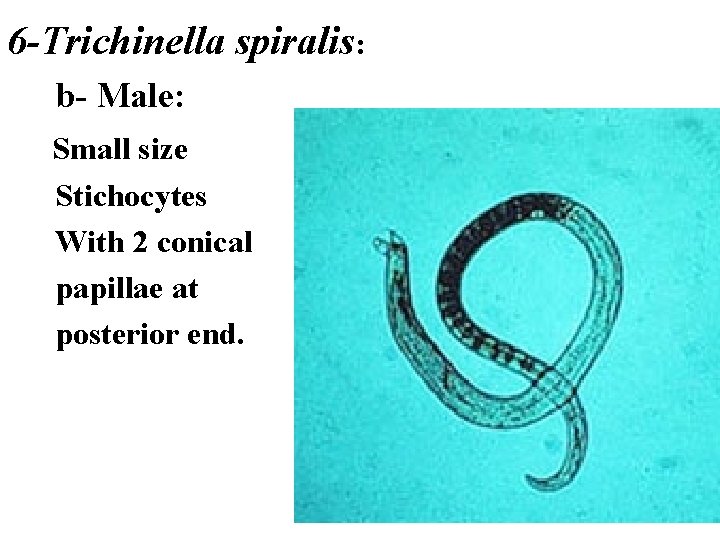

6 -Trichinella spiralis: b- Male: Small size Stichocytes With 2 conical papillae at posterior end.